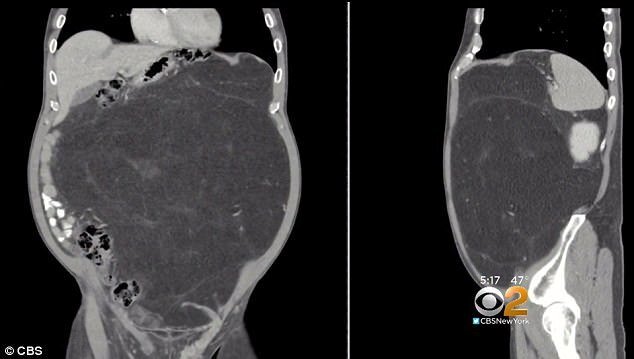

Mang khối u khổng lồ bao năm cứ ngỡ là bụng bia

Các bác sĩ Bệnh viện Lenox Hill, bang Manhattan (Mỹ) cắt bỏ khối u nặng tới 13,6kg cho người đàn ông 63 tuổi.